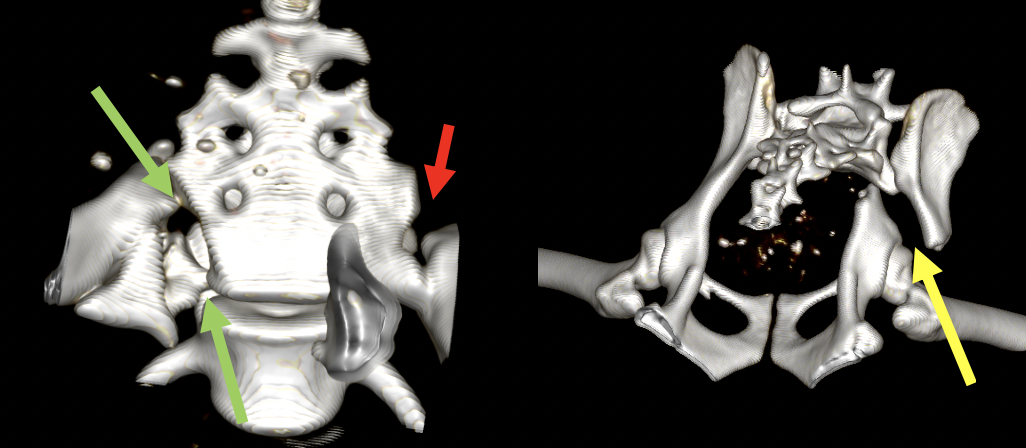

チワワの症例です。左右の仙腸関節が脱臼(正確には左は仙骨骨折)しています。緑は左の仙骨骨折、赤は右の仙腸関節脱臼、黄色は右の腸骨骨折をさしています。

仙腸関節脱臼と、仙骨骨折はボルトとアンチローテーションピンで止めてあるのと、腸骨翼にロングボルトというものを入れて狭窄を予防しています。また、右の腸骨の骨折にはパールプレートと呼ばれるプレートを入れて固定しています。